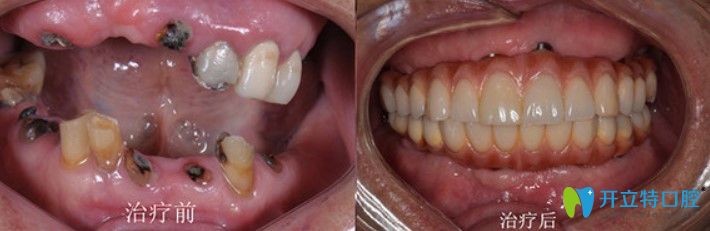

劉大爺,63歲

牙齒情況:全口牙齒脫落

種植方式:微創(chuàng)即刻種植技術(shù)